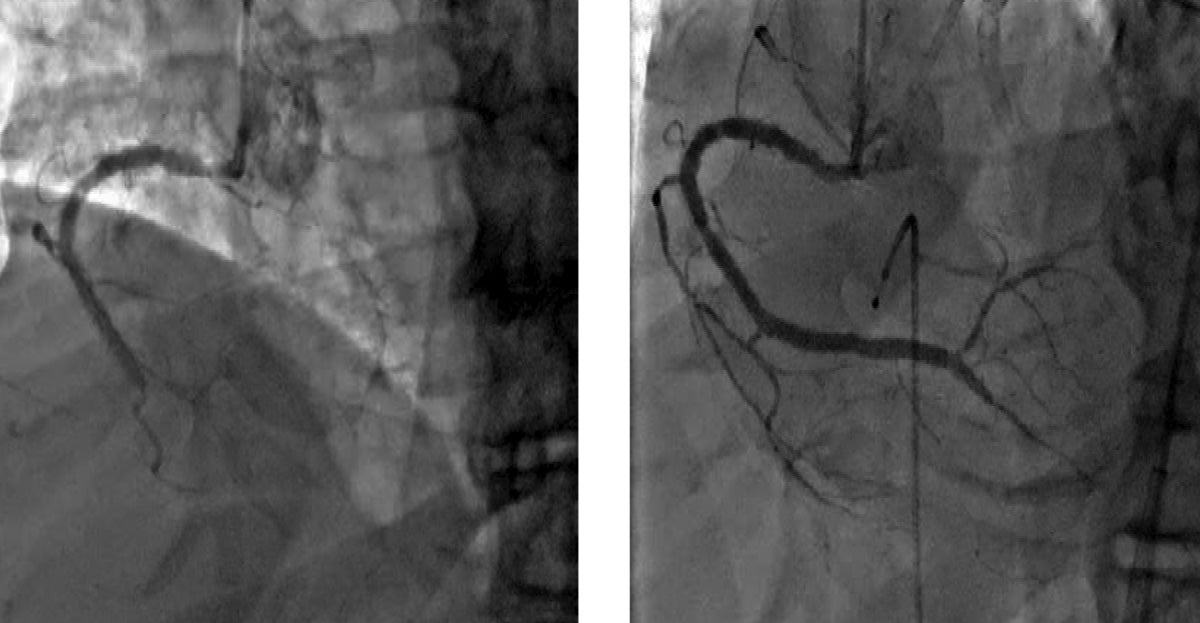

Picture this: An individual comes into a doctor’s or clinician’s office with symptoms of chest pain, shortness of breath and fatigue. The doctor or clinician orders a cardiac catheterization procedure, which reveals that one artery has a 100 percent blockage.

“If a patient has been told, ‘You have a blockage but there’s nothing we can do about it,’ chances are it’s chronic total occlusion,” Dr. Patel says. “And, more importantly, chances are that the statement, ‘There’s nothing we can do about it,’ is inaccurate. Almost always, there’s something we can offer this patient to help them feel better.”